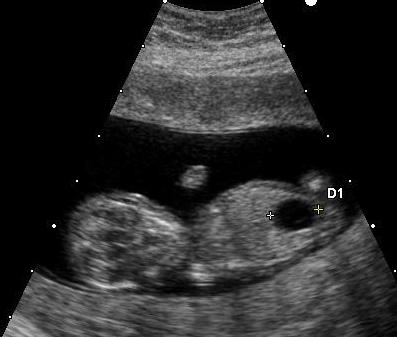

Fetal megacystis is characterised by an abnormally enlarged bladder visible on an ultrasound during pregnancy. It’s most often detected in the first or early second trimester, when the baby’s bladder can be visualised easily. Normally, the fetal bladder fills and empties regularly, a sign that the baby’s urinary system is working well.

In megacystis, the bladder remains persistently enlarged, often measuring more than 7 mm in length before 14 weeks of gestation. This typically suggests that urine is being produced but not emptied efficiently, indicating a possible issue in the lower urinary tract.